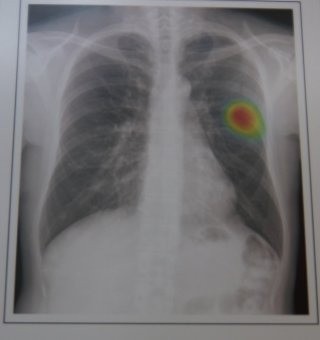

주요 증상과 진단

폐 섬유증의 증상은 매우 점진적으로 나타난다. 초기에는 운동 시 가벼운 숨가쁨 정도에 그치지만, 질환이 진행되면 계단 몇 칸만 올라가도 숨이 차고 일상 활동이 힘들어진다. 밤에는 마른기침이 지속돼 수면의 질이 떨어지고, 만성 피로감이 동반된다.

산소 교환이 원활하지 않으면 손끝이나 입술이 푸르게 변하는 청색증이 나타나기도 하며, 말기에는 산소통 없이는 생활이 어려워진다. 폐 섬유증은 폐에 국한된 질환이 아니다. 만성 저산소 상태가 지속되면 심장이 이를 보완하기 위해 과도하게 작동하면서 폐동맥 고혈압이나 우심부전 같은 심혈관 합병증으로 이어질 수 있다.